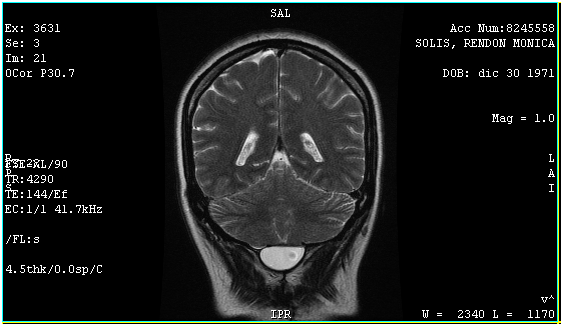

El 6 de agosto regresé con los resultados de la resonancia, análisis de sangre y orina, esta vez yo tuve los resultados primero, así que al verlo lo primero que dije fue "¿Qué pasa doctor que mi cuerpo sigue rechazando el parche?", la resonancia confirmó lo mismo el quiste media 4.2 x 1.7 x 2.9 cm y 10 centímetros cúbicos y la fistula 4.8 mm y el remanente del tumor es de 15.1 mm, en contraste con en el ultrasonido 4.1 x 3.0 x 1.6 cm y 11.04 centímetros cúbicos y la fistula 0.7 cm.

Afortunadamente el doctor estaba de mejor humor, porque mientras veía los resultados me contestó "Su cuerpo es muy chocosito que quiere, esto no tiene nada que ver con las cirugías, de eso está perfecta", me mostró que el remanente del tumor alojado en el tallo cerebral y cree que mi falta de equilibrio y náuseas tienen que ver más eso. El tallo cerebral regula las funciones vitales lo que significa que mi falta de equilibrio será permanente, de las náuseas no lo sabe.

"El quiste no ejerce ninguna presión en cerebelo o tallo cerebral, y el resto está perfecto no hay ningún daño" "Supongo que algo tiene que hacer con la fístula, no me puedo quedar así o sí?", "Bueno, no representa peligro alguno, ya que es la misma agua circulante, pero vas a regresar al medicamento que reduce el líquido del cerebro, usa la venda en las noches para hacer presión, evita cualquier esfuerzo o cargar cosas pesadas, porque solo generaría presión, en un mes vienes y vemos si se redujo el quiste y cerró la fístula y evaluamos si te ponemos una válvula".